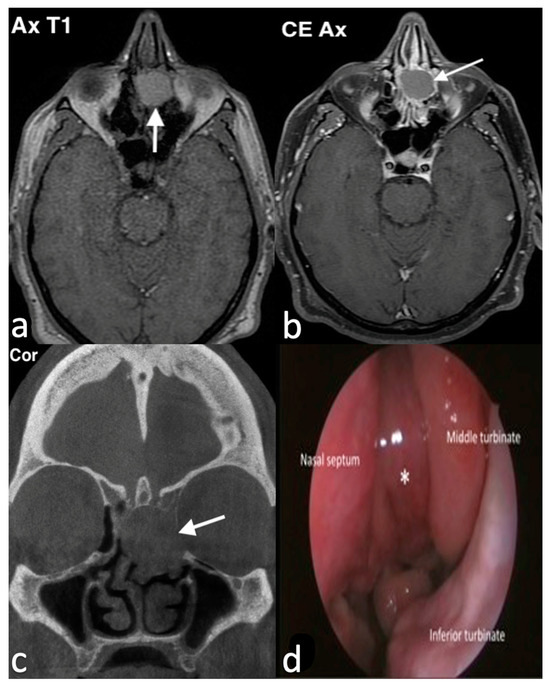

3.1.1. Septal Mucocele

3.1.2. Rinolith

3.1.3. Inverted Mesiodens